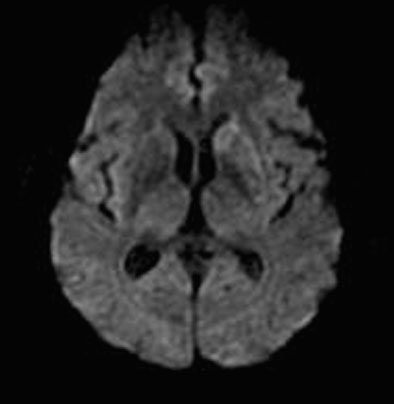

| Diffusion-weighted MRI obtained immediately after perfusion CT demonstrates only a slightly hyperintense region in the left basal ganglia. Images courtesy of Dr. Sotirios Bisdas. |